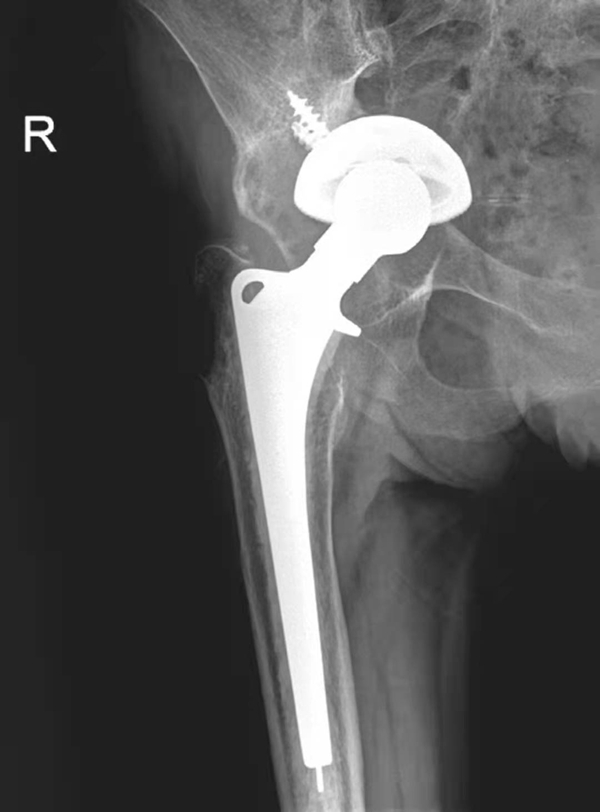

二、感染

人工髋关节置换术后感染是常见而又极其严重的并发症,感染经久不愈及扩大将导致死骨形成及假体松动。X线检查主要有以下几方面表现:①假体周围出现透亮带,透亮带轮廓不规则,宽窄不等,呈花边样,部分伴硬化边缘;②假体出现松动移位;③股骨柄髓腔内、外侧骨质破坏伴死骨及骨膜新生骨形成(图4);④行造影时有腔道与关节相通。以上征象有时难以和无菌松动区别,结合临床上出现局部红肿热痛,可考虑深部感染的存在。

图4 右侧人工髋关节置换术后感染并松动

女性,89岁。发现右大腿中段后侧流脓2个月余。平片,示右股骨上段骨密度增高,内侧骨膜增生,假体周围骨质吸收,髋臼杯内陷,人工股骨柄部内移